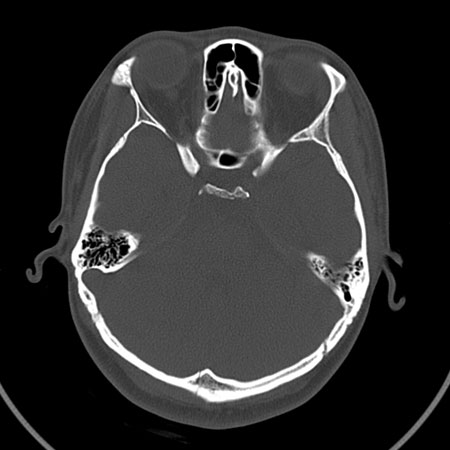

请问各位战友:图示箭头处是否为颅骨骨折?

病史:患者,女,20岁.头部及腹部外伤20分钟.伤后昏迷,无呕吐.头及右侧腰背部疼痛,双侧瞳孔等大,

右肾区叩痛.其它无异常.患者家属否认原有外伤史.

请大家看看是否为颅骨骨折.还是正常变异,或为陈旧骨折.谢谢.

枕骨的线样低密度影锐利、清晰,但正好位于矢状缝的位置,局部无明显软组织肿块,相临及对冲部位脑实质亦无出血及挫裂伤表现。

单就这几层暂不考虑骨折,建议上传完整图片。

楼主所关心的另一个线样影应该是头颅矢状面略偏左,射线正好穿过所致,不需要考虑骨折。

枕骨是单块的,矢状缝是在顶骨而不是在枕骨,枕骨后缘见线状低密度,边缘税利,考虑在骨折存在。

枕后部及左侧颞枕部边缘锐利的线样低密度影,局部软组织无异常,左侧乳突蜂房密度均匀,硬膜下及脑实质内未见出血灶,考虑为正常变异。

枕部锐利透亮线,可以考虑枕骨骨折.左侧枕颞缝。

枕部考虑骨折。一般的颅逢不会跨越板障,楼主所示枕骨断面两侧板障也不连续。

枕骨骨折,另外一处不考虑骨折

上图

箭头1:骨缝

箭头2:骨折不能排除